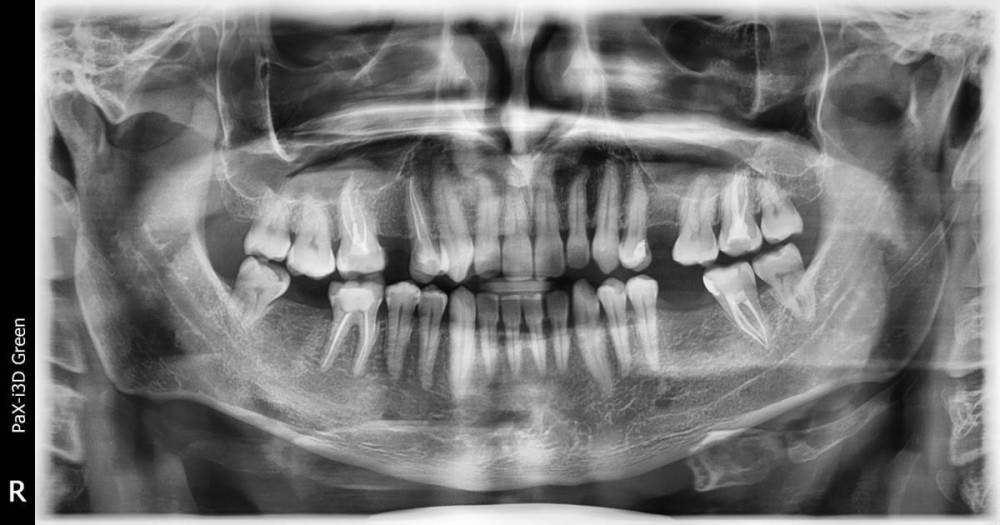

bufc1 Опубликовано 27 января, 2022 Поделиться Опубликовано 27 января, 2022 (изменено) Здравствуйте недавно появилась боль в районе левой верхней семерки,которая была депульпирована 4 года назад.Болит в районе 6-7-8-ого зубов ,больше 6-7. Был у врача ,врач предложил сделать КТ на предмет 4-ого канала в семерке. Cделал КТ Верхней челюсти на томографе Vatech,в другой стоматологии ,там где я делал КТ позже посмотрел врач и по телефону объяснил ,что в левой семерке есть 4 канал и небольшое воспаление,а также в правой шестерке 4 канал и воспаление ,она депульпирована 10 лет назад,но она меня не беспокоит пока. Но на панорамном снимке сделанном около 12 месяцев назад воспаления в правой шестерке не было.Может на КТ артефакт? слишком большое воспаление. Посмотрите пожалуйста КТ на предмет 4-ого канала в 7-ке слева и 6-ке справа ,что делать с этими зубами?,а также если не сложно состояние остальных зубов на ВЧ? Свежий КТ https://disk.yandex.ru/d/bhzap_ENY_BKyg Панорамный снимок около года назад Спасибо. Изменено 27 января, 2022 пользователем bufc1 Ссылка на комментарий

bufc1 Опубликовано 2 февраля, 2022 Автор Поделиться Опубликовано 2 февраля, 2022 (изменено) Посмотрите пожалуйста если есть возможность КТ , зубы 16 и 27 . По поводу 16-ого сказали там киста,странно ,что ее не было год назад на панарамном снимке,зуб депульпирован 10 лет назад. А в 27 зубе 4-ый канал врач не видит. Сейчас лечу 24 зуб ,удалили нерв и будут пломбировать каналы . 1) Что делать с 16 и 27 зубами? 2) Планирую начать имплантацию , установить пока один имплант,врач советует начать с установки в район 36 зуба. Как вы считаете правильно? Изменено 2 февраля, 2022 пользователем bufc1 Ссылка на комментарий